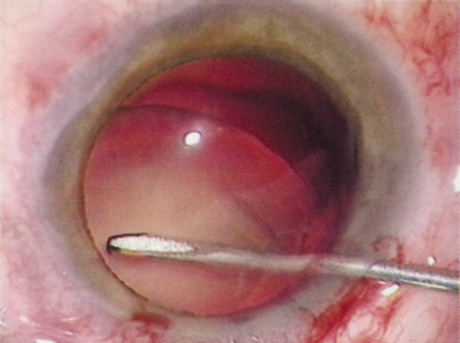

| There are many different approaches to disassembling the lens nucleus; each

level of experience. Slow-Motion Phacoemulsification Slow-motion phacoemulsification is a technique that seeks to maintain a stable anterior chamber during phacoemulsification while minimizing the volume of fluid that flows through the eye. By minimizing fluid inflow, there should be less endothelial cell loss and, therefore, less early postoperative corneal edema. Additionally, low inflow levels decrease the chance of forcing fluid through any areas of weakened zonules, which could create fluid lacunae within the vitreous gel, leading to positive pressure and possible vitreous prolapse. Chamber collapses are less likely because vacuum levels and aspiration rates are low; therefore, the risk of iris damage or posterior capsule rupture should be diminished. Because the technique involves low vacuum, aspiration, and inflow, it may be difficult to hold onto nuclear fragments for some methods of chopping the nucleus. Divide Techniques Divide techniques attempt to emulsify the nucleus by separating it into two or four pieces. Grooves carved into the nucleus facilitate separation of the pieces. The grooves can be achieved using low vacuum levels because complete occlusion of the phacoemulsification tip during is neither needed nor desired at this stage of the procedure. If one makes the groove at least twice the diameter of the phacoemulsification tip, there is better visualization of the walls of the groove, and thus better understanding of the groove's depth. A wide groove also results in the surgeon debulking more of the nucleus in the capsular bag, so that when the pieces are brought forward, less emulsification needs to be performed anteriorly. While fashioning the groove, it is important not to move the phacoemulsification tip faster than it is emulsifying. Advancing the tip too quickly causes the entire nucleus to move with the tip and may lead to subincisional zonular damage. The groove depth required to allow cracking depends on the density of the central and posterior nucleus. A hard nucleus with a dense posterior plate may not crack even if grooved through 90% of its thickness. Likewise, a fetal nuclear cataract may be cracked easily after grooving only halfway through. Regardless of the depth of the groove, the surgeon should place the cracking instruments at the most posterior aspect of the groove before dividing. (Fig. 17). Doing so minimizes stress on the anterior capsulorrhexis and generates forces more likely to result in a successful divide. After the nucleus has been bisected, the surgeon can debulk and emulsify each heminucleus separately. Alternatively, the surgeon can rotate the nucleus 90 degrees and further divide it into quarters in a similar fashion. After the surgeon has completed the divide portion of the procedure, vacuum and aspiration levels can be increased. By increasing vacuum and aspiration levels, the surgeon will find it easier to bring nuclear pieces to the phacoemulsification port. Additionally, higher vacuum levels hold the nuclear segments more tightly to the phacoemulsification port, resulting in more efficient phacoemulsification and better control. ”Chop” Techniques In 1993, Kunihiro Nagahara introduced a method of chopping the nucleus into pie slice–shaped wedges for emulsification (Fig. 18). Chopping techniques can be defined as vertical or horizontal chopping. Both chopping techniques involve burying the phacoemulsification tip into the center of the nucleus, holding it in place with increased vacuum. When performing a vertical chop, the chopping instrument is inserted through a second incision and placed beneath the anterior capsular rim. The chopper is directed peripherally, and then drawn posteriorly and centrally toward the phacoemulsification tip, causing the nucleus to crack. The horizontal chop differs in that the chopper does not need to be placed under the anterior capsular rim and the chop does not begin at the lens periphery. Instead, the chopping instrument is placed in the nucleus near the anterior capsulorrhexis edge and then directed posteriorly until it meets the buried phaco tip. Both chopping techniques take advantage of the natural cleavage planes between the nuclear lens fibers, similar to chopping a piece of wood with an ax. Each wedge can be brought centrally using a second instrument or the vacuum of the phacoemulsification tip for emulsification away from the posterior capsule, iris, capsulorrhexis edge, and bag periphery. Then the nucleus is rotated and similar maneuvers are performed with each segment until the entire nucleus has been emulsified. Smaller, more manageable wedges can be chopped off the nucleus for dense nuclei and larger pieces sectioned from softer nuclei.